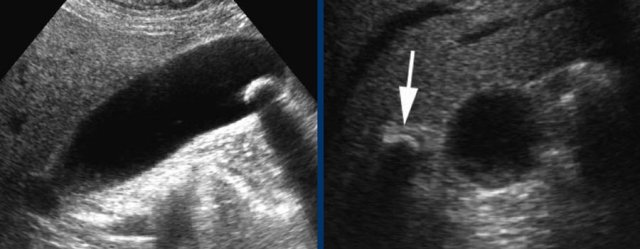

Here two examples of impacted stone visualized during biliary colic in different patients.

In the supine position a stone (arrow) is demonstrated in the gallbladder neck.

After standing up, bending over and walking, the stone (arrow) does not fall down, and therefore must be impacted.

Stones in the cystic duct are sometimes not demonstrable in the US plane of the longitudinal axis of the gallbladder.

Here images of a patieny with acute hydrops due to an impacted stone.

The impacted stone could not be visualized in the longitudinal axis of the gallbladder, due to its medial position in the cystic duct (arrow).